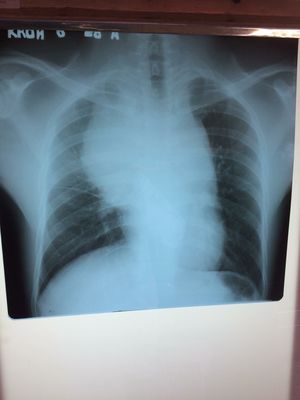

🏥 Case report from Pneumo Department KSFH. 📡 Personal information: Man 24 years old from Koh Kong Province. 📡Cc: Dyspnea associate with minimal chest pain 📡 ATCD: - Secondary smoking exposure - working in industry over 6 years (រោងចក្រផលិតឥដ្ថ) - No previous treat Anti-TB - Non previous tumor - Non surgery - No coagulation disease - No previous kidney or liver disease 📡 Presentting illness: His symptom developed over 5 months ago with Dyspnea associate minimal chest pain. He detail more about his symptoms, it's just start aggravating for several day especially Dyspnea, it's always occur during he work or exertion. He used to use medication to pain relief but it did not improve until now. It's the main reason entry to the Pneumo Department KSFH. 📡 PE report: - GA: mild condition - Consciousness: Alert - Minimal chest pain with score pain around 3 (EVA 3) - Dyspnea type polypnea with SpO2: 93% Air environmental and RR: 28 - RS and TF decrease on R side - Rhythm irregular with Tachycardia (HR: 94 B/min) - Hemodynamic stable with BP report 110/8mmHg - Abdominal soft and stool normal - Urine normal - No Adenopathy detection - No edema - Other system normal 🏥 Questions: depend on case reported 1. Dx probability and initial management...? 2. What's second step to confirm Dx...? 3. If Dx of imagery suspected CA, which next step do you need to perform.....? 4. What the most type of CA on this patient (Common CA) 5. If Dx positive has been confirm, what's is your management on Patient....? 6. Prognostic and Advice to patient and family....? 7. Survival rate....?